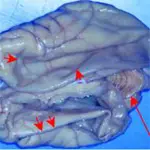

The brain of a dog diagnosed with hydrocephalus. The cerebellum is normal in appearance (long arrow), but the cerebral cortex is very thin.When the cranial cavity was opened, the dilated lateral ventricles collapsed, causing the thin layer of cortical tissue to fold in on itself (short arrows).